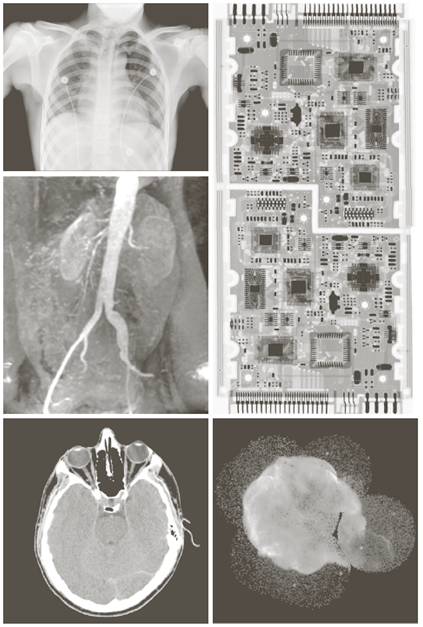

X-ray image

a) 항암제 Taxol b) 콜레스테롤 c) 마이크로프로세서

Visual band image – 영상처리에 의한 품질검사

a) 회로 기판

b) 포장 알약

c) 병

d) 플라스틱 표면의 기포

e) 씨리얼

f) 각막 이식

Other imaging modalities

- 전자현미경: SEM(scanning electron microscope)

- 전자빔을 쏘아 각 위치에서 빔과 샘플과의 상호작용을 기록

텅스텐필라멘트의 250x SEM영상, 손상된 IC의 250x SEM영상